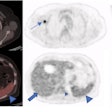

PET/CT shows impact of different COVID-19 vaccines

December 18, 2023